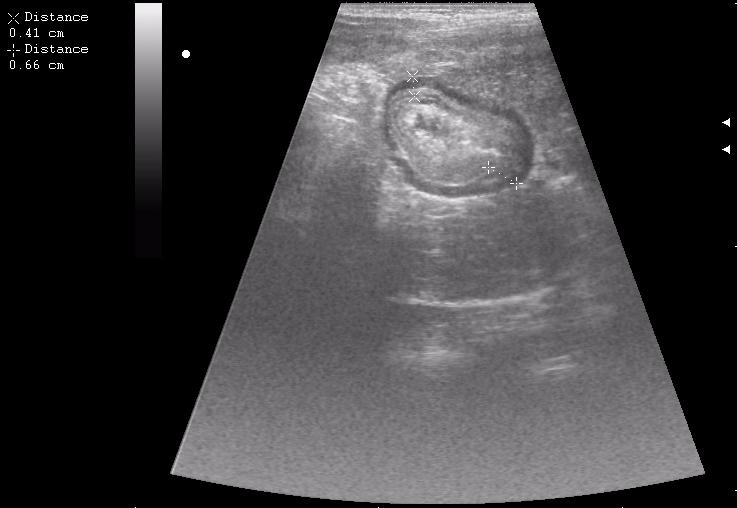

конец рабочего дня тоже "порадовал". Травма об руль велосипеда.

30 мин. после травмы